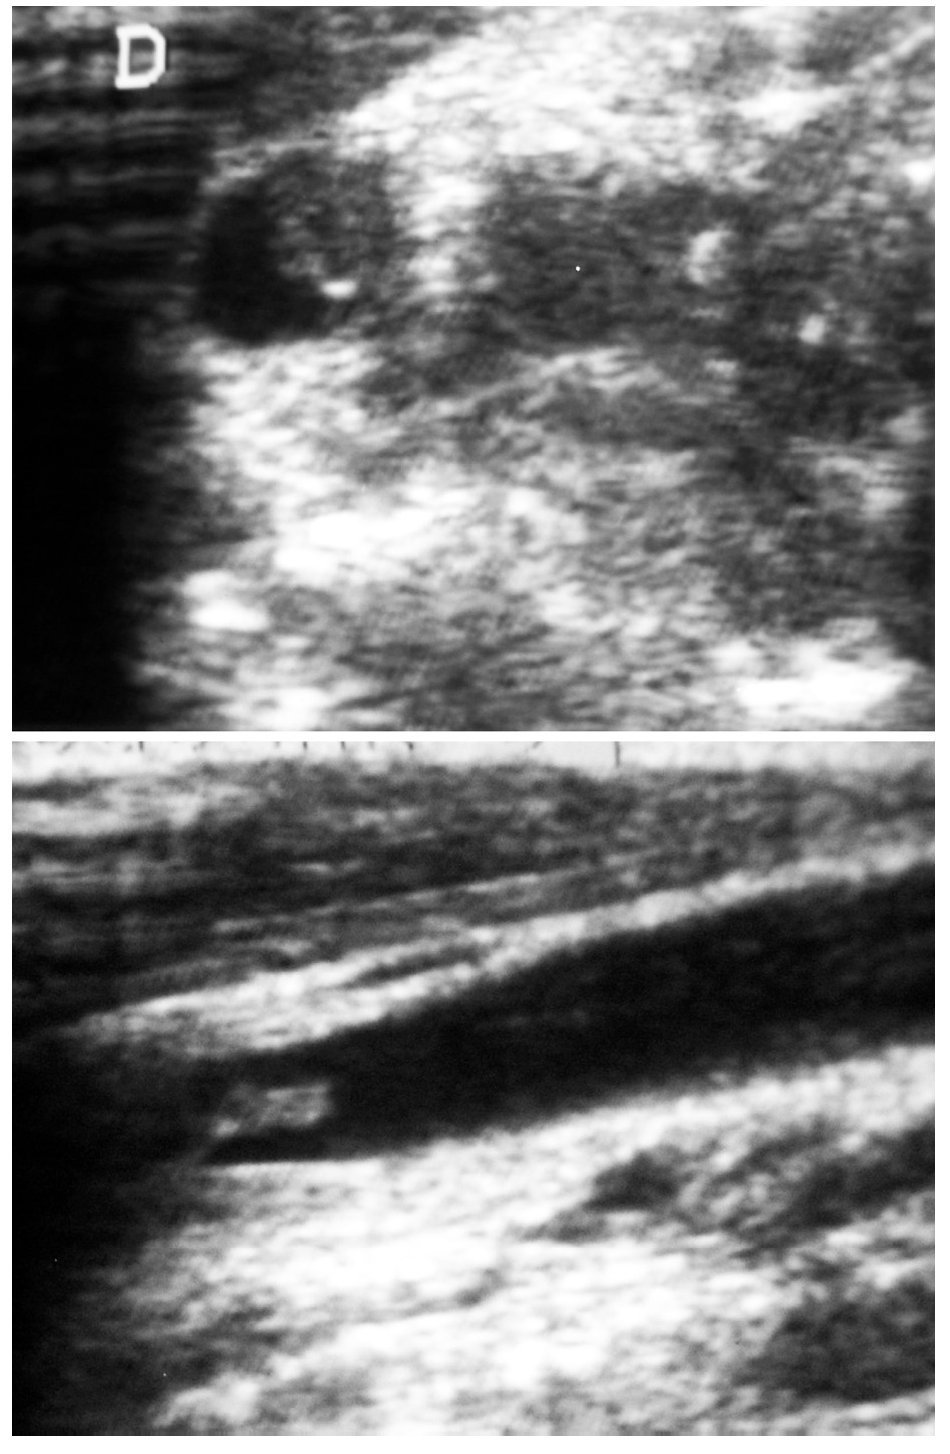

Fig. 4. Vena yugular interna. Ecografía cervical.

Se realizaron pruebas de imagen consistentes en radiografía simple de tórax y senos paranasales, tomografía computarizada de tórax, ecografía abdominal y ecografía doppler cervical.